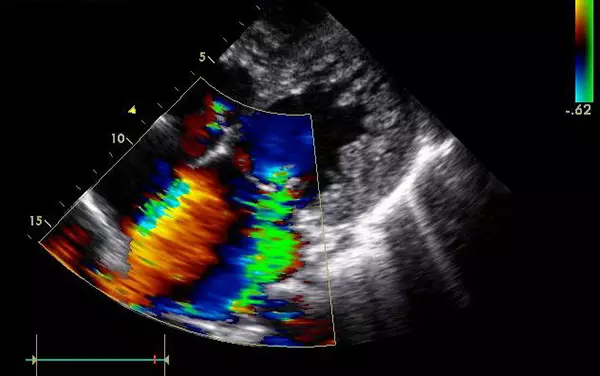

B超

B超的原理是用超聲波穿透人體,當(dāng)聲波遇到人體組織時會產(chǎn)生反射波,通過計(jì)算反射波成像。

優(yōu)點(diǎn):多方向觀察,實(shí)時成像。

缺點(diǎn):超聲受氣體干擾很大,對于腸道等含氣較多的器官,超聲診斷準(zhǔn)確率會降低,所以一般腸道檢查使用腸鏡。

(B超下胎兒在媽媽肚子里)

5、心臟——排除冠心病用CT,看心功能用超聲